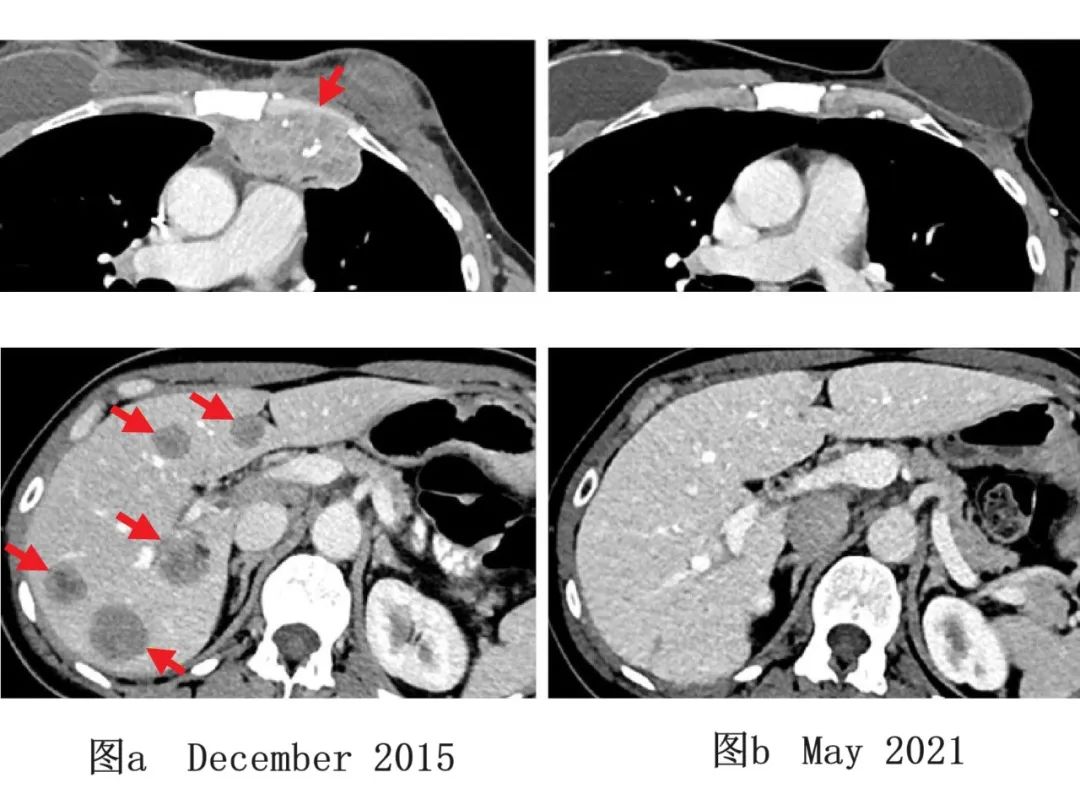

图2 1例乳腺癌患者TIL治疗前后影像学变化

图a:患者治疗前(2015年12月)影像学检查示,肝脏(下,左)、胸壁(上,左)处,均有转移性病变。

图b:患者经免疫治疗后(2021年5月)影像学检查示,肿瘤完全缩小,随访5年未出现新发癌症。